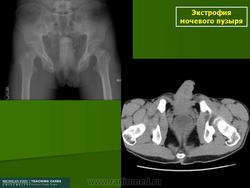

Экстрофия мочевого пузыря.

Приложения:

1.ekstr_.slayd156.jpg1.eestr_.slayd120.jpg